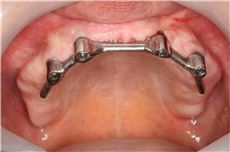

implant&total prosthesis